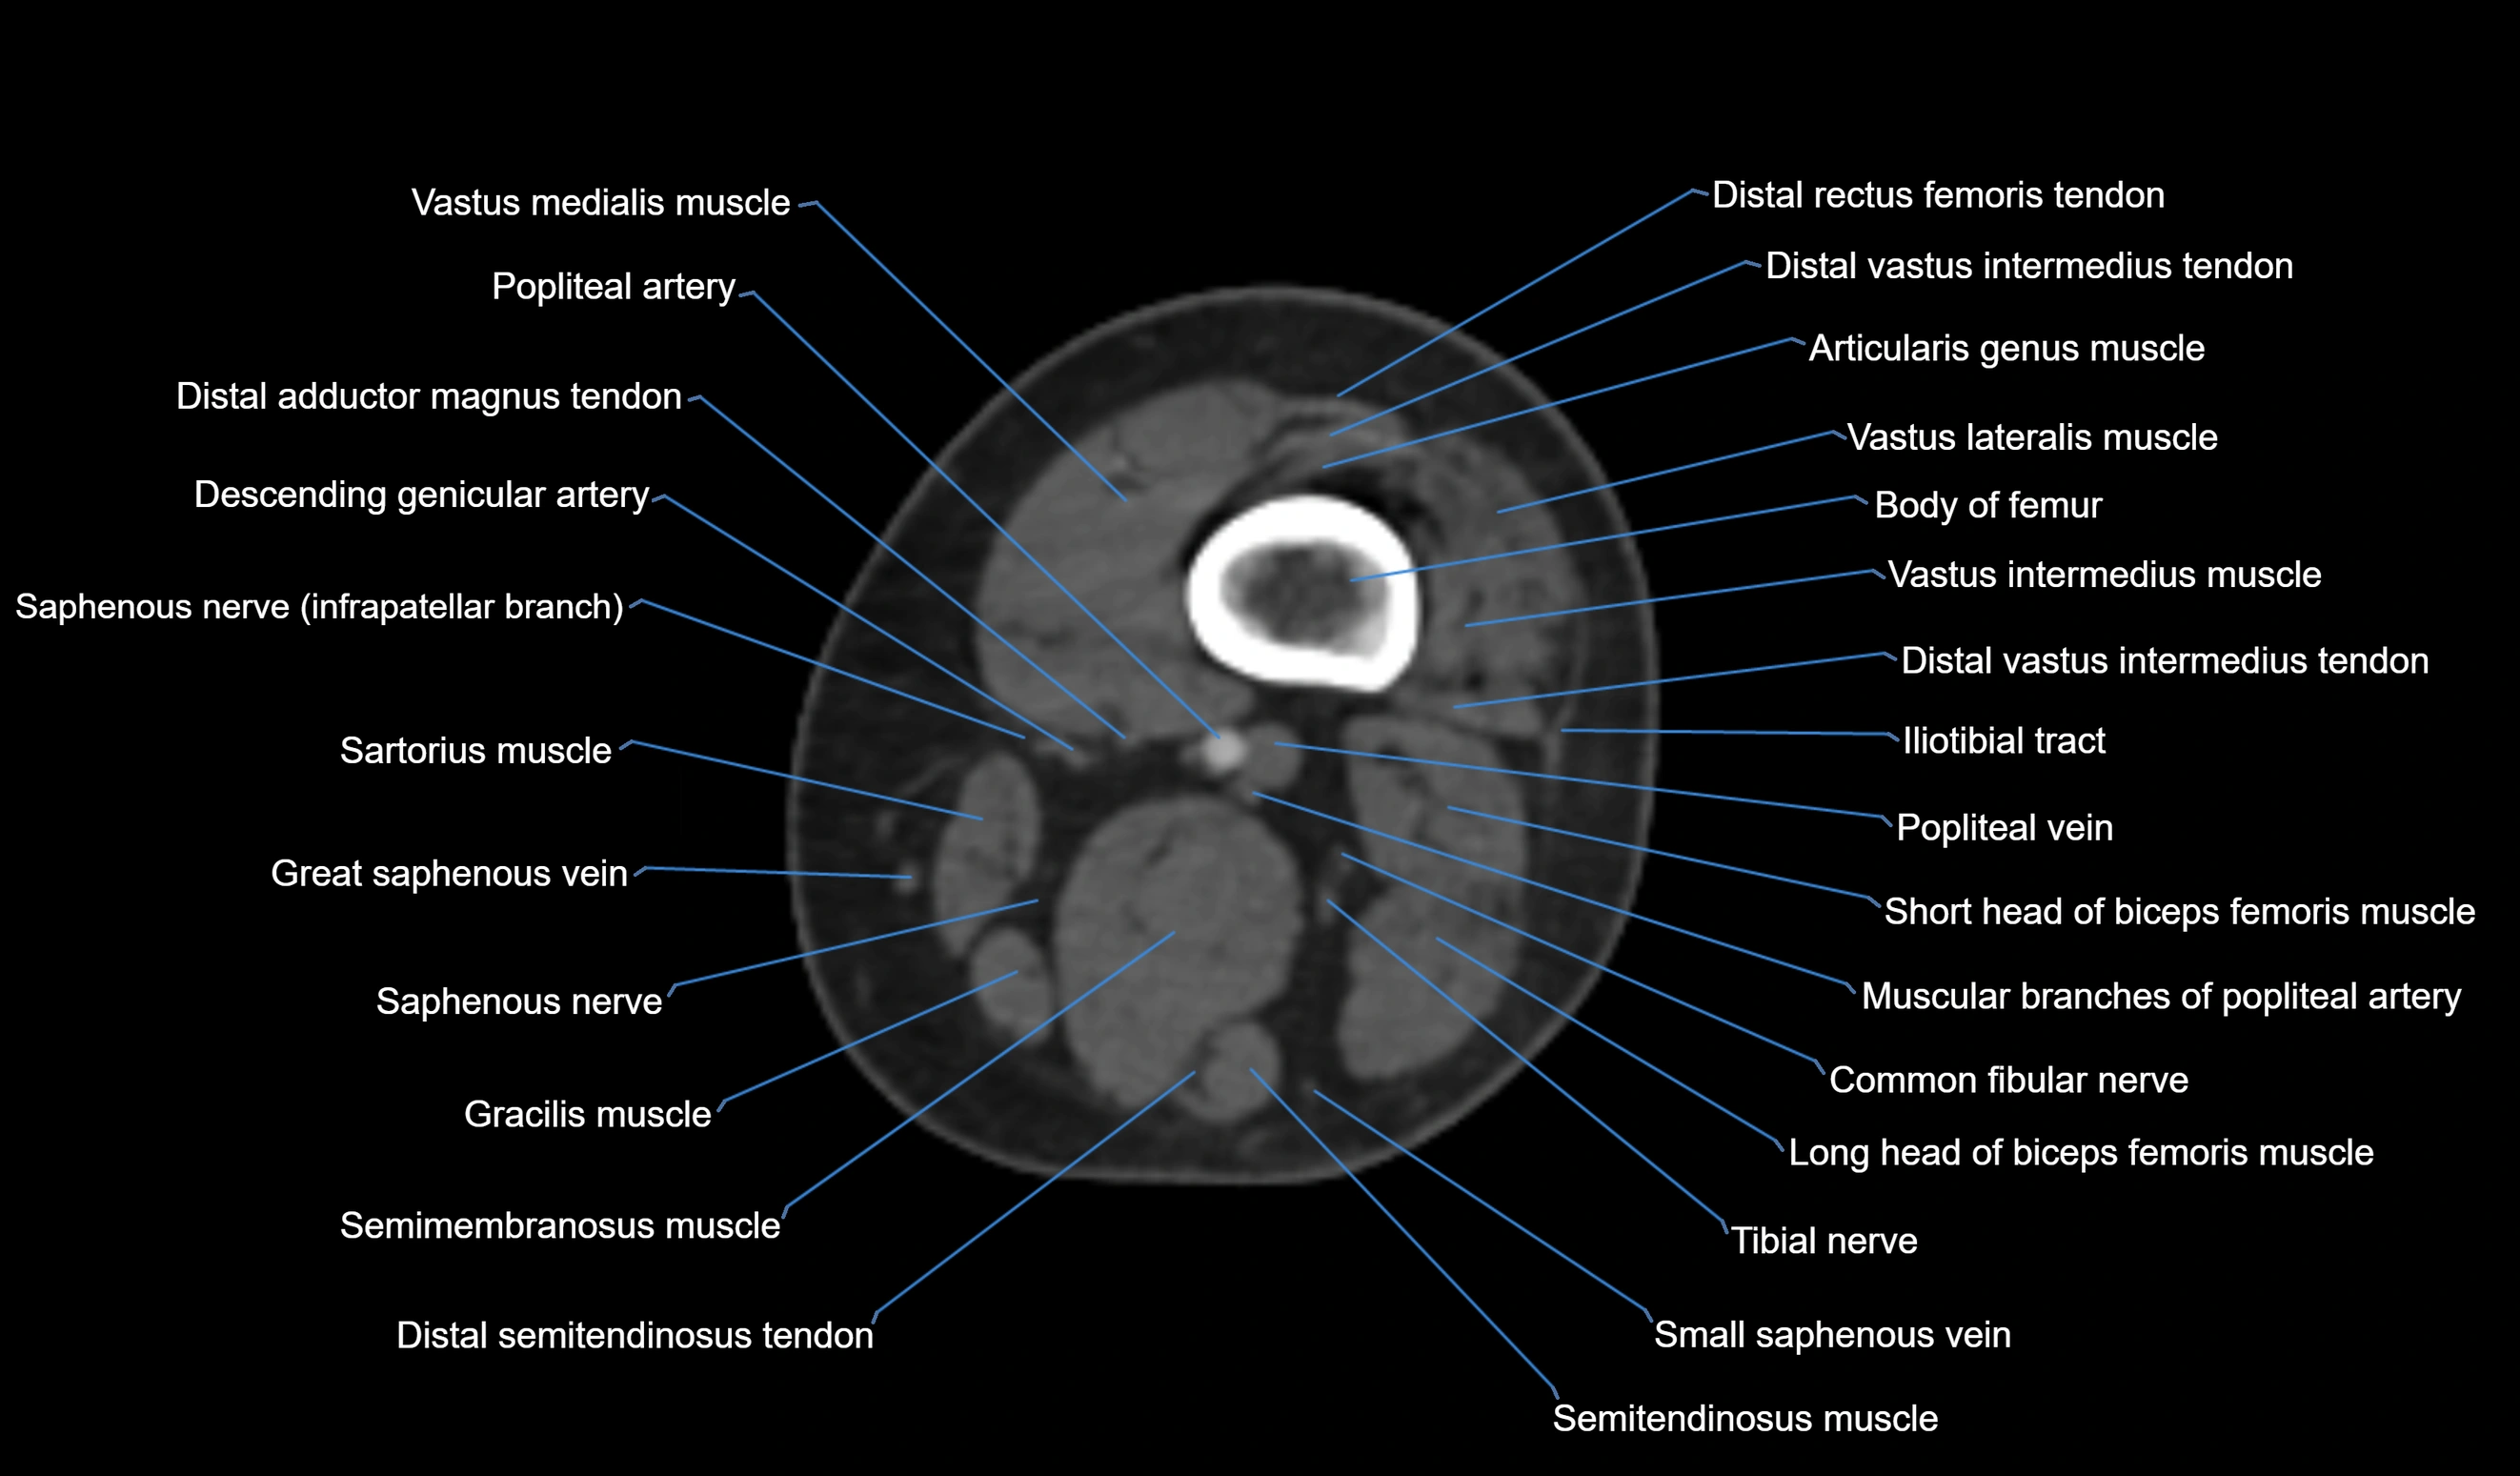

- Body of femur

- Common fibular nerve

- Descending genicular artery (Articular branches)

- Distal adductor magnus tendon

- Distal rectus femoris tendon

- Distal vastus intermedius tendon

- Popliteal artery

- Popliteal vein

- Saphenous nerve

- Sartorius muscle

- Semitendinosus muscle

- Tibial nerve

- Vastus lateralis muscle

- Vastus medialis muscle

- great saphenous vein